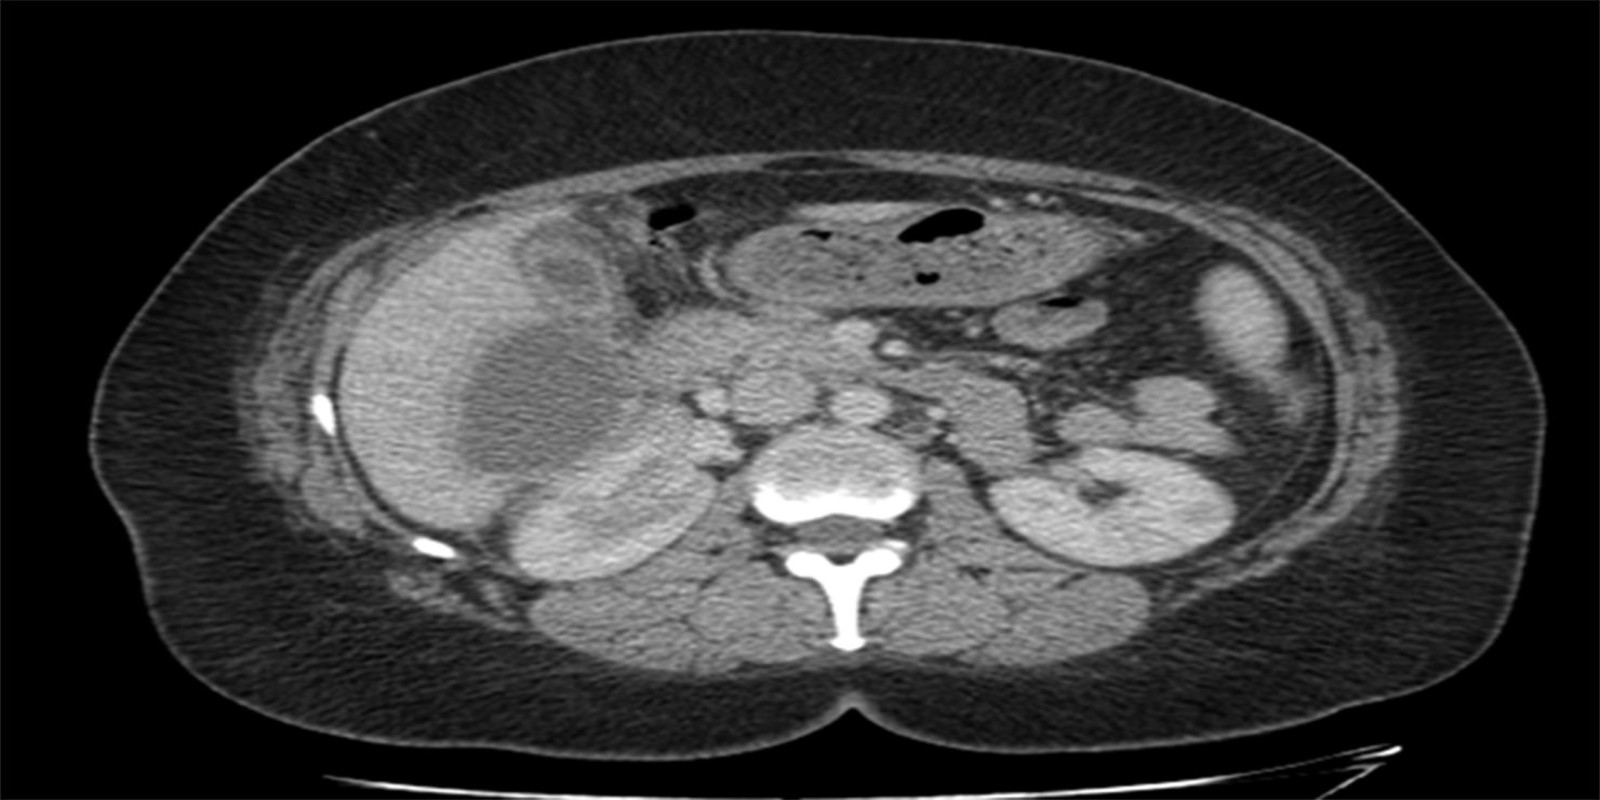

Caso Código 148A de Colecistite Aguda

Cod.: 148A